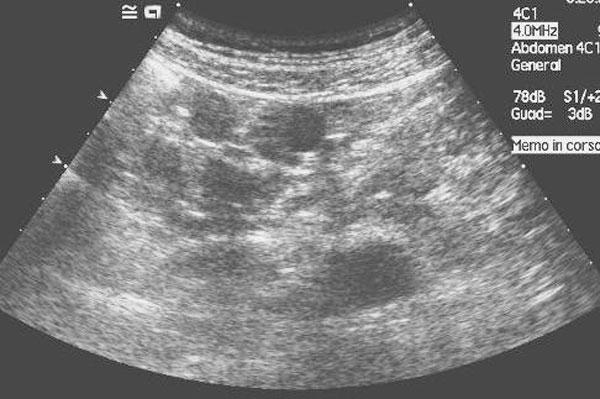

A 56-year-old man with history of persistent hematuria from bladder cancer was referred to our Institution for suspected peritoneal carcinosis. For staging purposes he underwent abdominal computed tomography and ultrasound. The integration of patient's history and imaging results led to the diagnosis of peritoneal splenosis. The patient therefore underwent regular Trans Urethral Resection of Bladder for the known malignancy; while no treatment was necessary for splenosis. Two years follow-up was negative for metastases.

一名56岁男性,有膀胱癌导致持续性血尿病史,因疑似腹膜癌转移被转诊至我院。为进行分期评估,他接受了腹部计算机断层扫描和超声检查。综合患者病史和影像学结果,诊断为腹膜脾组织移植。因此,该患者因已知的恶性肿瘤接受了常规经尿道膀胱肿瘤切除术;而脾组织移植无需治疗。两年随访未发现转移。